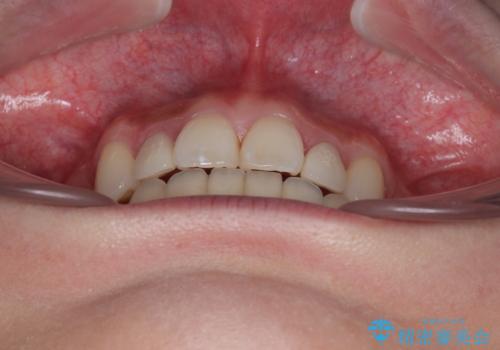

飛び出した前歯 インビザラインを用いた抜歯矯正治療

- 前方に飛び出した前歯を気にして来院された患者様です。

遠方の地元へ転居する予定があるとのことで、インビザラインによる治療を希望されていらっしゃいました。

上下前歯同士の距離が離れているため、上顎左右第一小臼歯2本を抜歯することで前突を改善することとしました。

しかしながら、左右ともに側切歯が矮小歯であるため、矯正治療で矮小歯前後にスペースを作り、矯正治療後にオールセラミッククラウンにて補綴治療を行うこととしました。

治療途中で地元へ転居され、飛行機での通院となったため、治療期間が長くなりましたが、自然で整った口元に仕上げることができました。